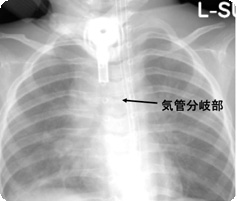

③ 単純X線写真でカニューレの位置を確認します。 |

気管切開 術後はPICUで鎮静 単体X線でカニューレの位置を確認 |